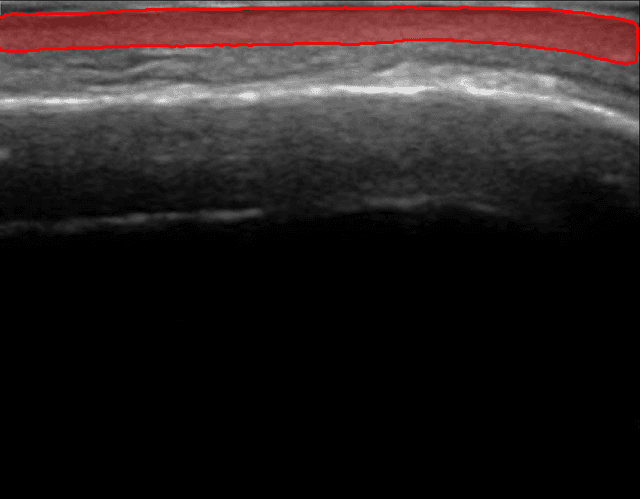

Escaneo de Precisión en 60 Segundos

Nuestra IA segmenta instantáneamente tu capa dérmica. Obtén mediciones precisas de el grosor y el área de la dermis.